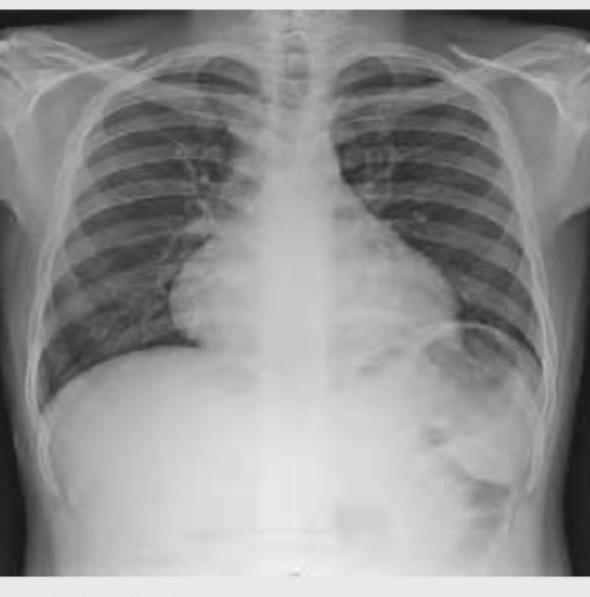

Question 6: Identify the congenital heart disease presenting with cyanosis in CXR: (Recent NEET Pattern 2016-17)

- A. Tetralogy of Fallot (Correct Answer)

Explanation: ***Tetralogy of Fallot*** - The chest X-ray shows a **boot-shaped heart** (coeur en sabot) due to right ventricular hypertrophy and a concave pulmonary artery segment, which is a classic finding in Tetralogy of Fallot. - This cyanotic congenital heart disease is characterized by four defects: a **ventricular septal defect**, **pulmonary stenosis**, **overriding aorta**, and **right ventricular hypertrophy**. *Truncus Arteriosus* - This cyanotic CHD involves a **single arterial trunk** arising from the heart supplying systemic, pulmonary, and coronary circulations. - CXR typically shows **cardiomegaly with increased pulmonary vascular markings** and a **right-sided aortic arch** in 30% of cases, not the boot-shaped heart seen here. - The pulmonary artery segment is **prominent or convex**, contrasting with the concave segment in Tetralogy of Fallot. *Ebstein anomaly* - This anomaly involves the **tricuspid valve** being displaced into the right ventricle, often leading to cardiomegaly and a **"box-shaped" or "globular" heart** on CXR, which is not depicted. - It can cause cyanosis, but the characteristic CXR finding is **massive cardiomegaly with diminished pulmonary vascular markings**, not a boot-shaped heart. *Snowman heart* - The "snowman heart" or **"figure of 8" sign** is characteristic of **total anomalous pulmonary venous return (TAPVR)**, specifically the supracardiac type. - This appearance is due to the dilated superior vena cava and the vertical vein draining into it, creating the "head" of the snowman, which is not seen in the provided image.